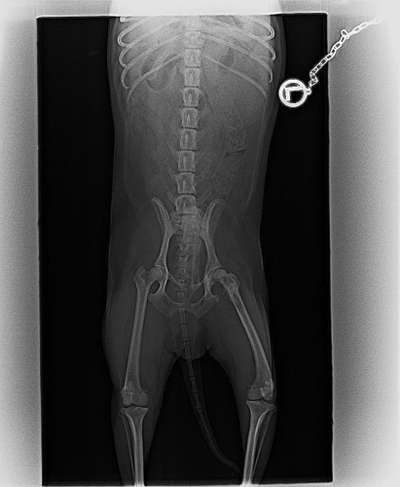

Hallo. Vor ca. 3 Wochen fing mein 10 Jahre alter Jack Russel an zu humpeln. Der Tierarzt sagte es wäre eine Entzündung im Rücken. Nach einigen Medikamenten wurde es einfach nicht besser. Nun waren wir wieder da und er wurde geröntgt. Auf Grund des Röntgenbildes wurde mir gesagt das es wohl ein Tumor ist. Kann jemand mit dem Bild etwas anfangen .. Einen Termin für ein CT haben wir erst am Montag bekommen. Solange halte ich es nicht aus.

Das Röntgenbild ist leider ziemlich schlecht aufgenommen. Die Hüfte ist darauf komplett schief und verzogen.

Man kann zwar eine Art Zubildung am rechten Kopf erkennen, was das aber ist, kann man wegen der schlechten Aufnahme unmöglich sagen.

So schief, wie die Hüfte ist, glaube ich nicht an Narkose.

Daher rührte meine Frage. Das ist meine Vermutung ebenfalls. Also kann man zusätzlich die Orthopädie nicht sicher beurteilen, was das Lahmen angeht …

Zwei Anhaltspunkte würde ich orthopädisch verorten möglicherweise, allerdings ist schwer zu beurteilen, ob es durch die nicht optimale Lagerung für die Bilder verursacht ist. Das CT und höher auflösende Aufnahmen können da hoffentlich mehr Klarheit bringen. Wenn sich der Verdacht eures Arztes nicht bewahrheitet (was ich hoffe, aber davon hab ich auch keine Ahnung tatsächlich), würde ich alle Bilder, insbesondere die besseren, einem Orthopäden zur Beurteilung zur Verfügung stellen.